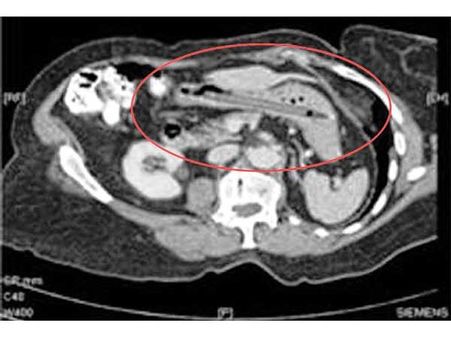

હેન્ડ ગ્રેનેડ

એક આંતકવાદીએ તેની બુદ્ધિનું પ્રદર્શન કરતા તેના શરીરમાં હેન્ડગ્રેન્ડ છુપાવી દીધા. પણ તપાસ વખતે આ ગ્રેનેડ દેખાઇ ગયો. અને તેની પોલ ખુલી ગઇ.